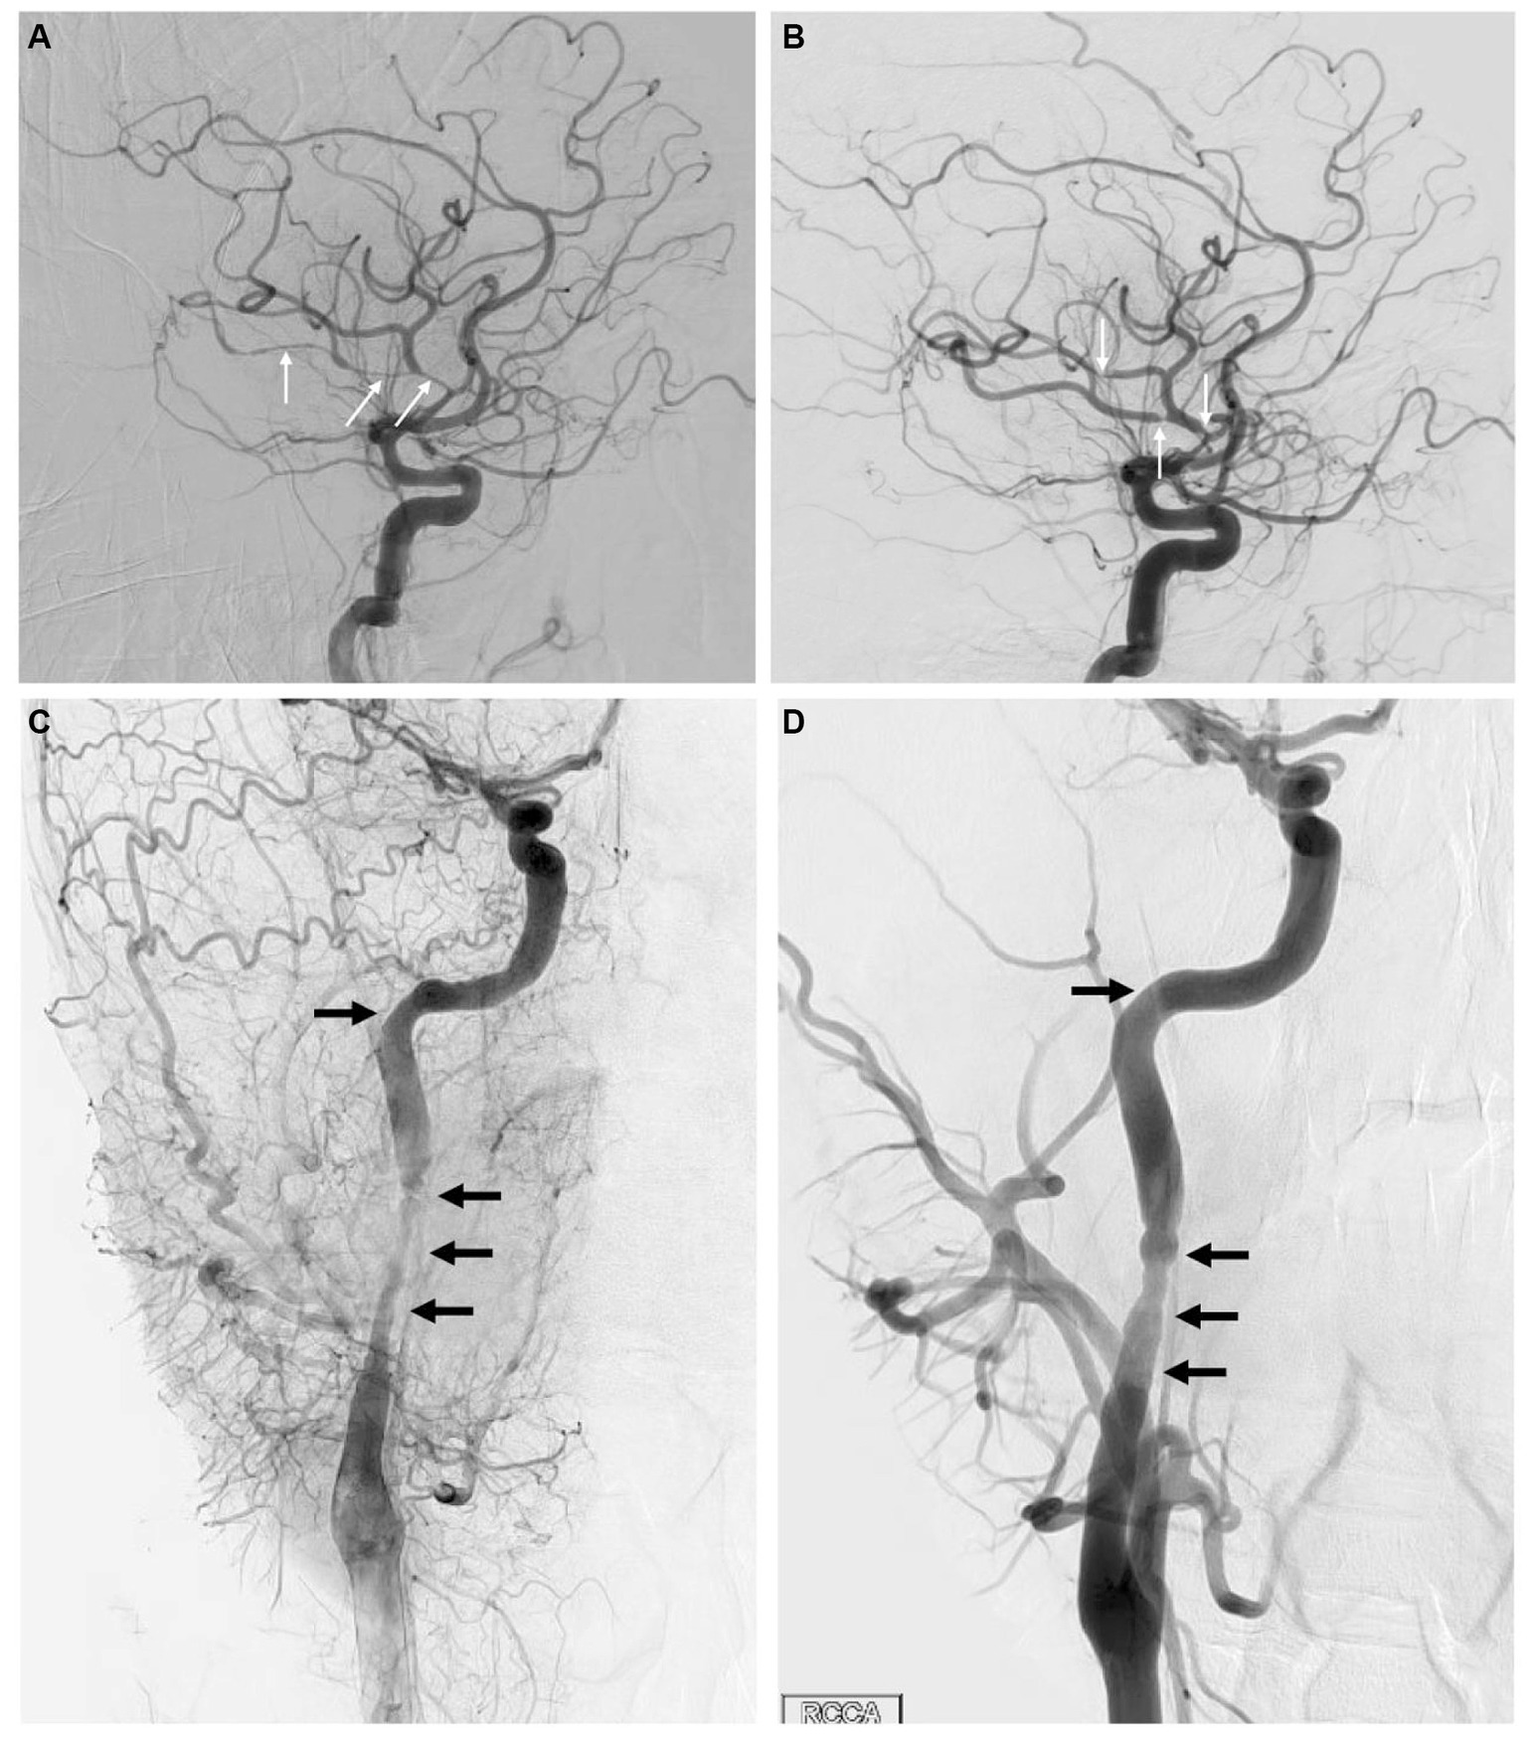

A 33-year-old man presented within an hour of symptom onset with sudden left hemiparesis, right gaze deviation, and confusion. Initial NIH Stroke Scale (NIHSS) was 15. CT head showed a slightly hyperdense right M1 (Figure 3A), confirmed to be a right middle cerebral artery (MCA) occlusion on vessel imaging. He was given tenecteplase at a local hospital, then transferred to a comprehensive stroke center for thrombectomy. Digital subtraction angiogram (DSA) revealed a persistent right M1 occlusion as well as a right A2 occlusion, but access was complicated by significant vasospasm with instrumentation of the internal carotid artery (ICA) (Figure 4C). After 1 pass with combined stent retriever and aspiration approach, there was successful TICI 2b reperfusion (Figures 3B,C). However, beyond the area of occlusion, multiple foci of vasospasm were noted in the MCA territory (Figure 4A). The patient was treated with 3 mL of intra-arterial (IA) milrinone for the MCA vasospasm. The balloon catheter was then retracted, and 5 mL of IA milrinone were given for the ICA vasospasm. After milrinone treatment, there was angiographic improvement of the vasospasm (Figures 4B,D).

Figure 4

(A) Lateral view of the right ICA injection on DSA, showing multiple areas of vasospasm within the MCA branches (arrows). (B) Same view following milrinone treatment, showing significant improvement in vasospasm with much shorter affected segments (arrows). (C) Lateral view of the cervical right ICA through a right CCA injection on DSA in the late arterial phase, showing significant vasospasm (arrows) within the proximal right ICA. (D) Same view following milrinone treatment, showing significant improvement in vasospasm (arrows).